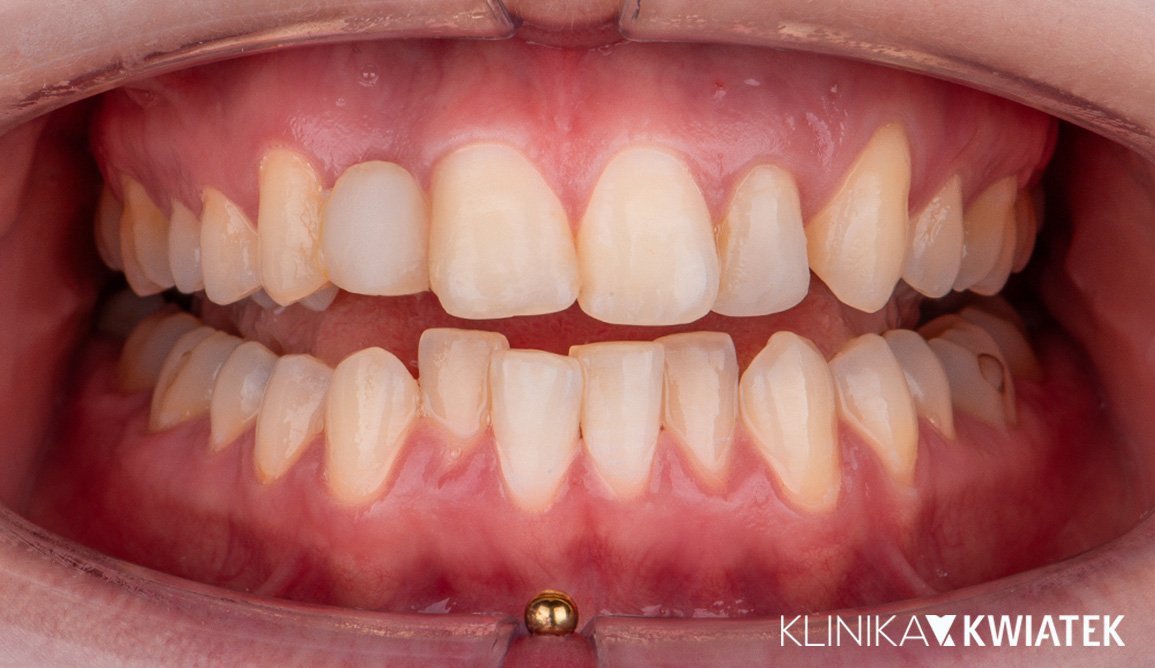

Pacjentka zgłosiła się z wadą zgryzu, licznymi ubytkami i utraconymi zębami trzonowymi, co powodowało trudności w żuciu i estetyczne niezadowolenie. Leczenie obejmowało ekstrakcje, ortodoncję, implantację oraz kompleksową rekonstrukcję protetyczną. Po kilkunastu miesiącach terapii Pacjentka odzyskała pełną funkcję zgryzu i piękny, harmonijny uśmiech.